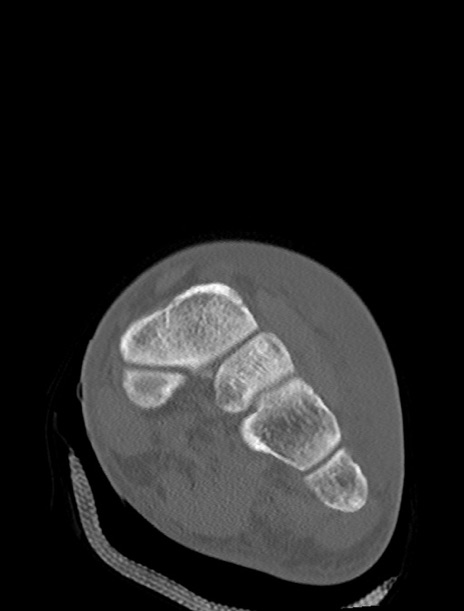

症例37 左足関節CT(冠状断像)

左足関節CT

3D再構成